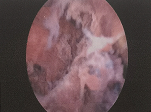

不查不知道,一查吓一跳——在宫腔镜下发现A女士的宫腔内充满了半球状、舌状、山峰状等形态各异的赘生物。

(患者宫腔镜术中记录图)

执行宫腔镜探查术的丁乃莉副主任医师当即在宫腔镜直视下,逐一切除宫腔内各赘生物,刮出子宫内膜,并将术中切除的赘生物送病理。